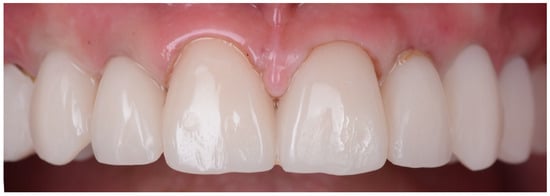

For the final restorations, monolithic zirconia was used for optimal biologic compatibility and superior strength (Figure 18a–f). The patient’s esthetics and function were fully restored. The intraoral pictures showed significant improvement in the micro esthetical characteristics. The gingival margins were levelled, and the teeth axes were corrected.

Figure 18.

Intraoral pictures of the result of monolithic zirconia-fixed partial dentures on teeth and implants: (a) upper incisors, (b) lower incisors, (c) right lateral view, (d) frontal occlusal view, (e) upper arch and (f) lower arch.

The extraoral pictures of the smile (Figure 19a,b) and of the face (Figure 20a–c) showed significant improvement in the dentolabial esthetics. The facial lower third was optimized due to the increased occlusal vertical dimension and slight posterior rotation of the mandible. The smile line became convex and parallel with the lower lip, while the profile became straight. The correct dental axes of the upper incisors improved the lip support.